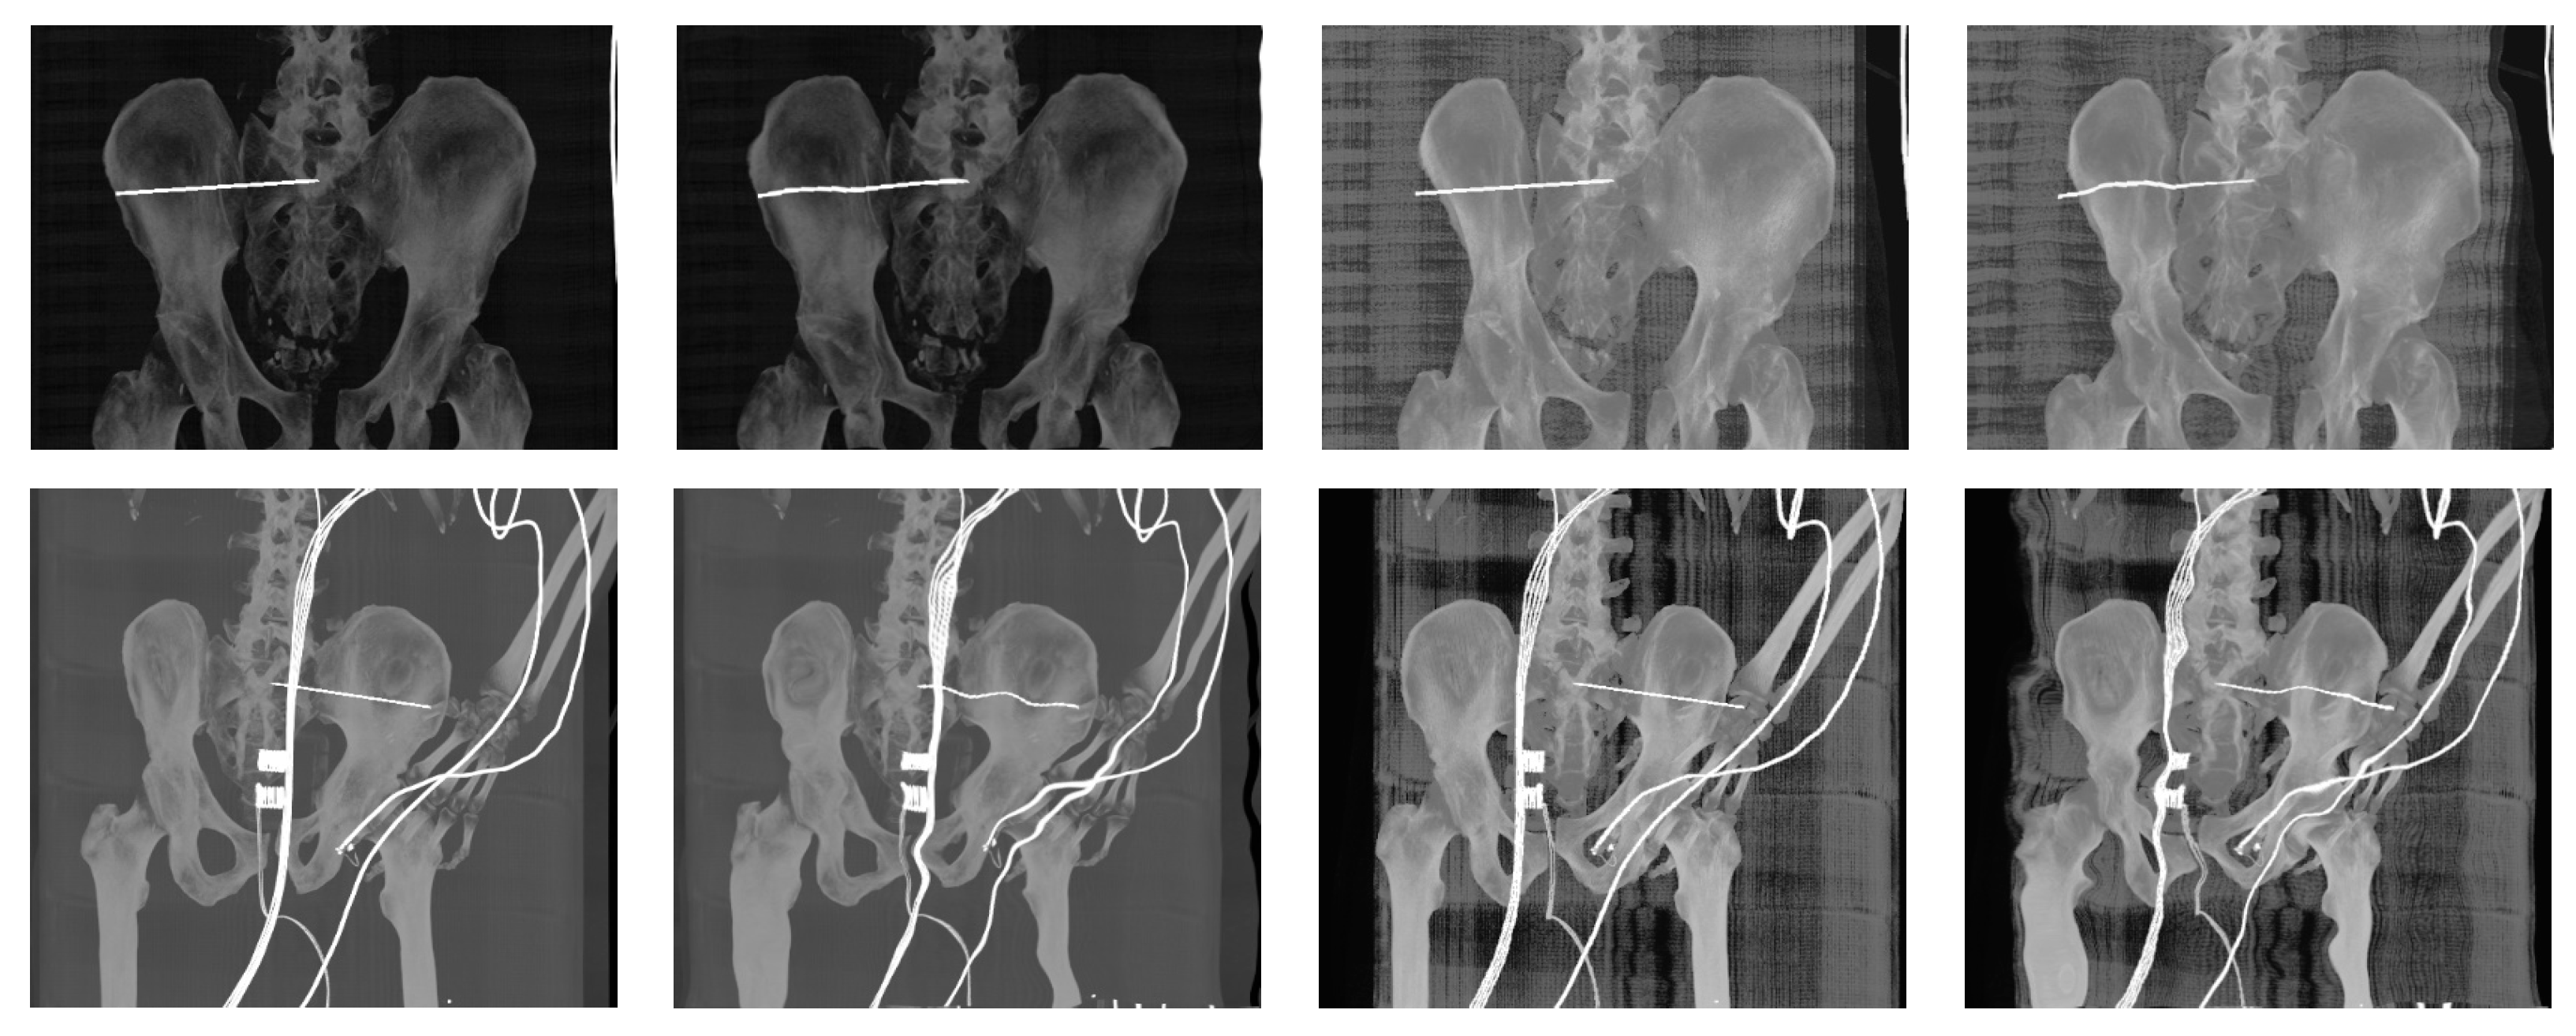

- Generation of digitally reconstructed radiograph (DRR) projections

- Multimodal image registration of DRR projections to a reference X-ray image